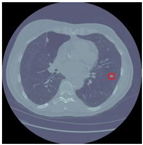

Table 12 demonstrates the results obtained from AlexNet with the SGD optimizer on the Luna16 dataset. The original image was benign, and the CNN architecture AlexNet with the SGD optimizer detected the image as benign. Next, the image was benign and AlexNet with the SGD detected the image as malignant, which was wrongly predict by AlexNet. The next image was malignant, and AlexNet with the SGD optimizer detected it as benign. Finally, the actual image was malignant, and AlexNet with the SGD optimizer detected it as malignant.

Table 12.

Detection results of AlexNet with the SGD optimizer on the LUNA16 dataset.